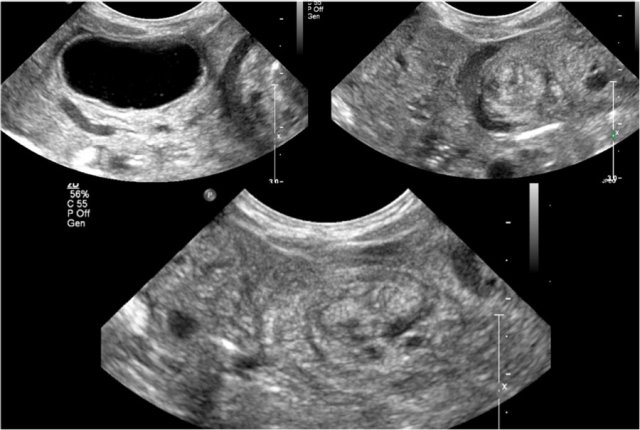

Here ultrasound images of a neonate who presented with an acute abdomen.

An ultrasound antenatally had detected a duplication cyst.

On the ultrasound there is a whirlpool sign of the vessels.

Torsion of the cyst and the mesentery had resulted in a volvulus.

This is a medical emergency and consequently the neonate went straight to the operating room.